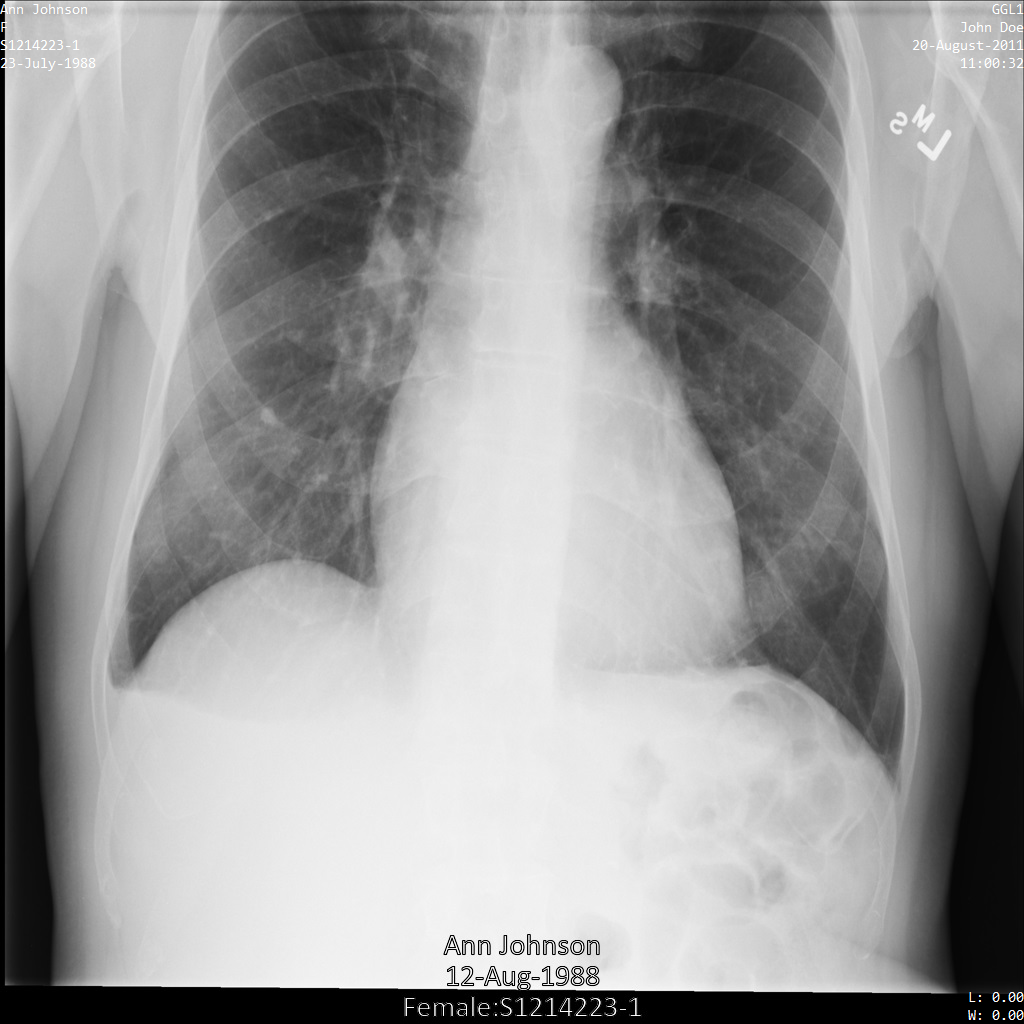

En la siguiente imagen se muestra una radiografía de un paciente sin censurar:

Después de enviar la imagen a la API Cloud Healthcare mediante la opción REDACT_SENSITIVE_TEXT, la imagen se muestra de la siguiente manera:

Puedes ver que ha ocurrido lo siguiente:

- El

PERSON_NAMEde la parte inferior izquierda de la imagen se ha ocultado - El

DATEde la parte inferior izquierda de la imagen se ha ocultado

El sexo del paciente no se ha ocultado porque no se considera texto sensible según los infoTipos DICOM predeterminados.